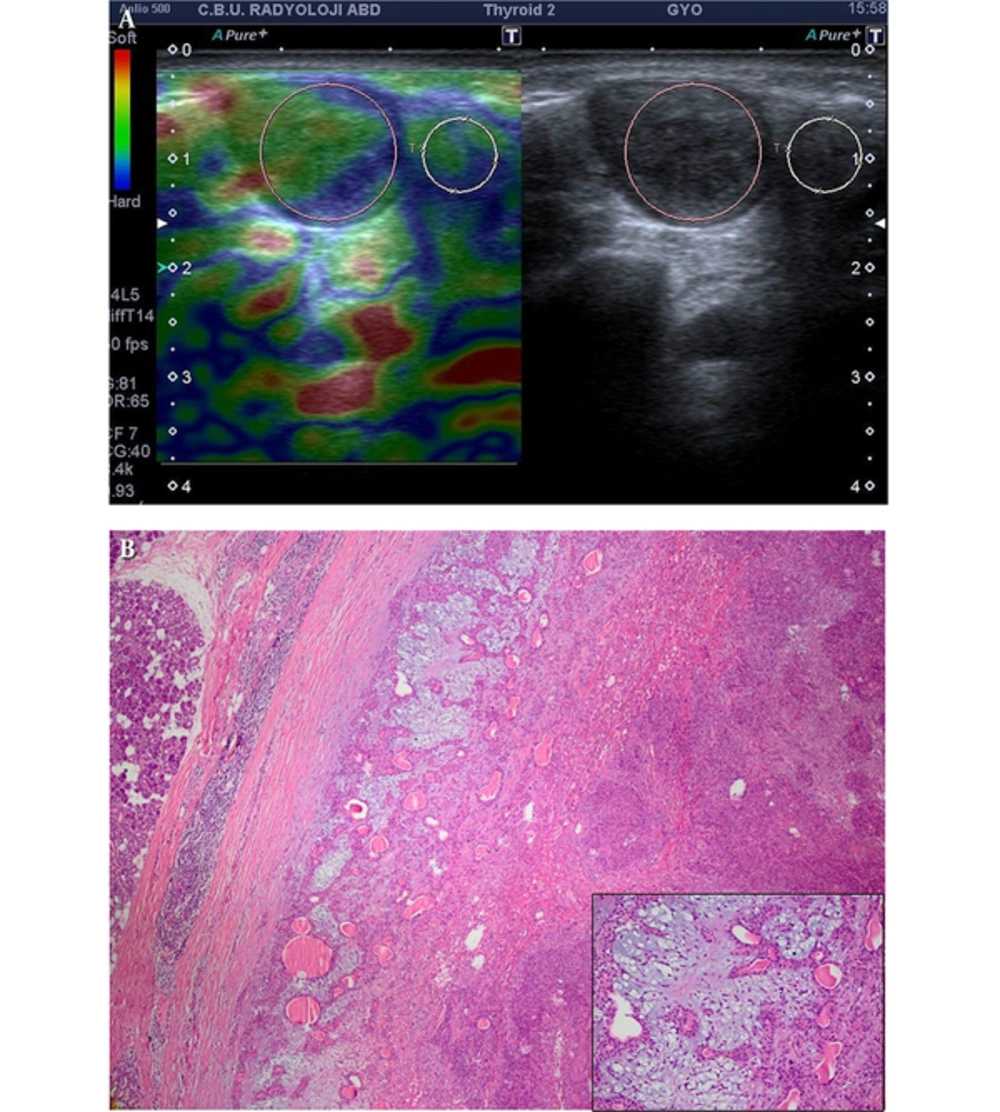

A, Pleomorphic adenoma: well-defined ovoid shaped and heterogeneous hypoechoic solid mass with milimetric cystic degenerations in left parotid gland mass which is predominantly soft. Strain ratio: 0.81, score of 2 lesion. B, Encapsulated and sharply demarcated tumoral lesion is composed of tubules, ductules and matrix stroma (H&E × 40); inset: myxoid stroma is remarkable admixed with acini and tubules (H&E × 200).